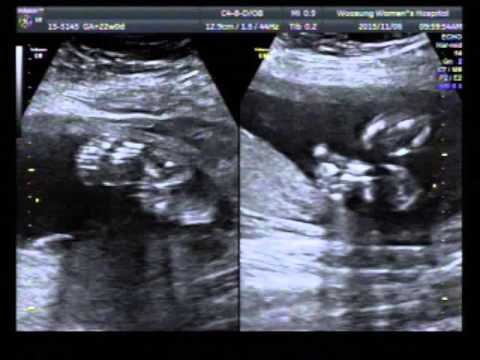

20 й неделе беременности

20 й неделе беременности 118 фотографий